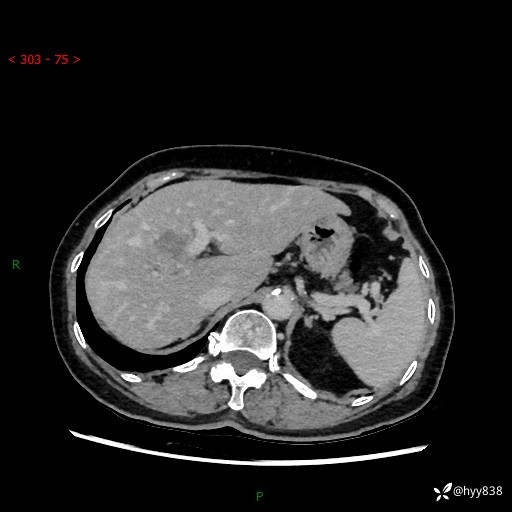

年龄:74岁

现病史:患者约半一周前常规体检发现肝占位,无恶心,呕吐,呕吐后症状不缓解,无畏寒,发热,无黄疸,无反酸,腹泻,胸闷等症状。现为求进一步治疗,遂来我院,门诊以“肝占位”收住我科。 患者起病以来,患者神清,精神可,饮食可,大小便正常,体重未见明显减轻。

既往史:结肠癌

上腹部CT平扫+增强